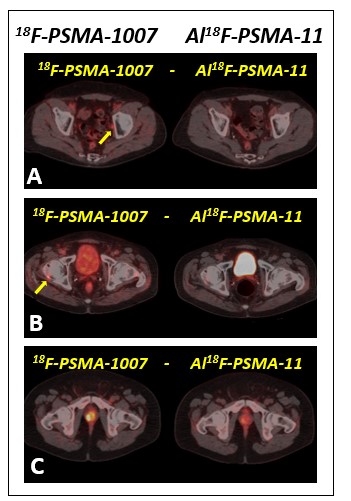

Figure 2: Axial PET CT images of three different prostate cancer patients showing metastasis in pelvic lymph node (A) and right femoral head (B) (yellow arrows) demonstrated only by means of 18F-PSMA-1007, and coincident prostate relapse (C). Note the better contrast and uptake intensity of 18F-PSMA-1007.